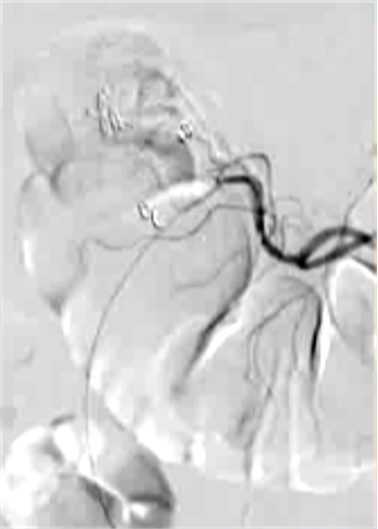

抗凝剂:肝素 溶栓药物:尿激酶、阿替普酶 ![]() 7 名患者 在动脉内内给予托拉唑啉、肝素、尿激酶进行血管造影操作 2 名患者出现出血性诱因情况 外科治疗 ![]() 回顾性分析(2002 年至 2008 年) 34 名患者(年龄 7 至 92 岁),36 例刺激性肠造影检查 全身性使用肝素 动脉内给药的血管扩张剂 11 名患者(占 31%)出现出血情况的检测结果。 10 栓塞治疗 病例1 消化道大出血 血压 70/40mmGg

病例三 77岁女性复发性胃肠道出血,需要多次输血并入住ICU。(d)栓塞后无外渗。箭头指向栓塞部位。